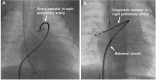

Transcatheter closure of patent ductus arteriosus (PDA) in premature infants is a feasible, safe, and an effective alternative to surgical ligation and may be performed with an implant success rate of 97%. Major procedural complications related to transcatheter PDA closure in extremely low birth weight (ELBW) infants are relatively infrequent (< 3%) ,but may be associated with a fatality if not optimally managed. Operators performing transcatheter PDA closures should be knowledgeable about these potential complications and management options. Prompt recognition and treatment are often necessary to avoid serious consequences. With strict guidelines on operator training, proctoring requirements, and technical refinements, transcatheter PDA closure in ELBW infants can be performed safely with low complication rates. This article summarizes the consensus guidelines put forward by a panel of physicians for the prevention and management of periprocedural complications of transcatheter PDA closure with the Amplatzer Piccolo Occluder in ELBW infants.